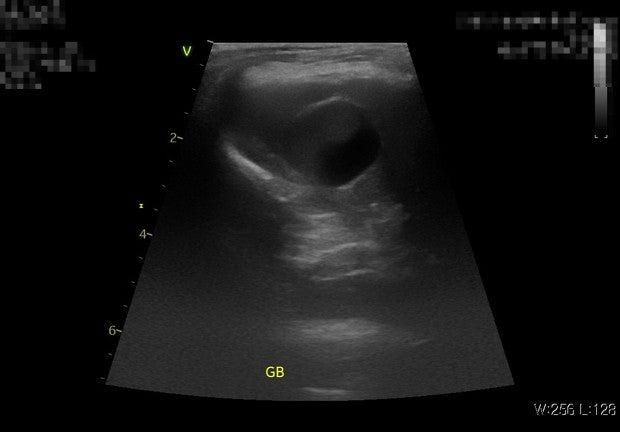

병원을 각기 다른 두곳을 다녔는데 모두 슬러지라 했으며 우루사 처방은 안해줬습니다 11살 토이푸들 4kg 수컷 강아지 입니다 ALP 수치 정상이였습니다

혹시 이 담낭 상태로 인해 부분적으로 겉에만 시멘트 회색변을 눌 가능성이 있을까요?

슬로지어도 다 수술하는 것이 아닙니다. 초음파나 혈액 검사 등으로 확실하게 탐랑 전액 좀 이 진단이 되는 경우에는 수술적인 담낭 제거술이 지시됩니다